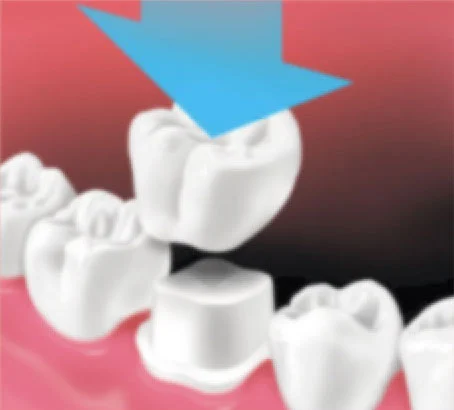

- When the permanent crown is ready, your dentist places it in your mouth and makes the necessary adjustments. When you and your dentist are happy with how it looks and feels, the crown is cemented into place.

Crown Placement

Crown is placed over prepared tooth